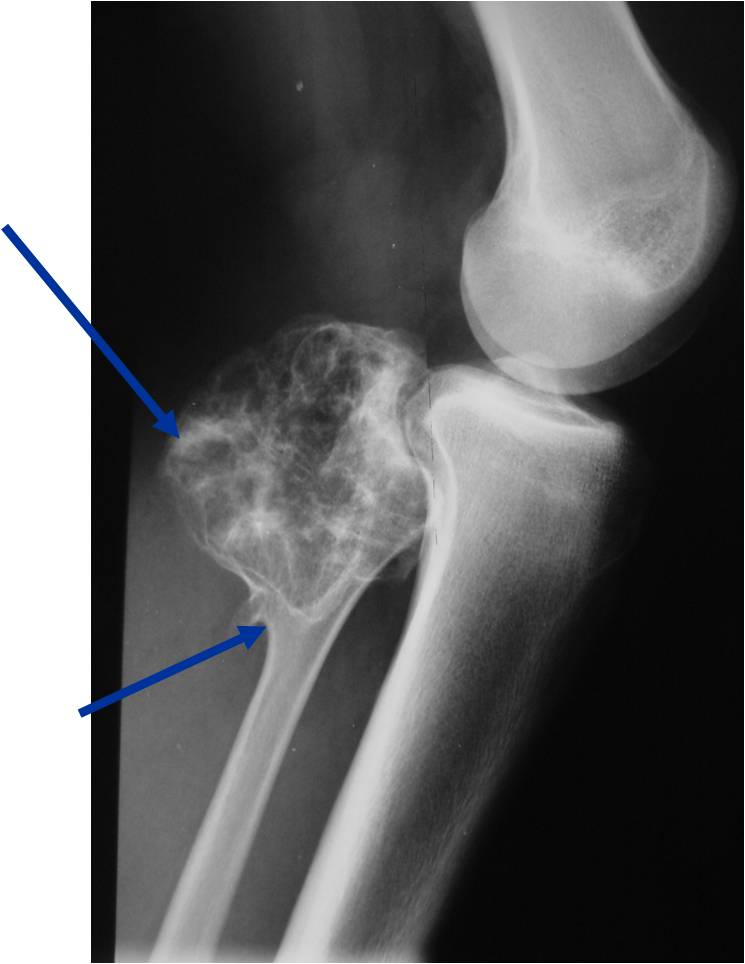

Plain X-rays:

- Projects from bone with narrow (pedunculated) to broad (sessile) stalk

- Corticomedullary continuity: Medullary bone continuous with that of osteochondroma and cortex blends with that of osteochondroma

- Calcification in cartilaginous cap (“Ring and Arc” and stippled calcifications)

- Lobular growth pattern

Plain X-ray: Secondary Chondrosarcoma of Proximal Femur